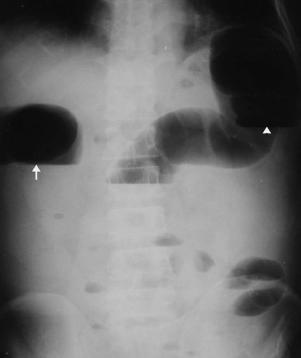

Image en

chapelet de l'intestin : Une aspect tres

particuliairement de l'occlusion de l'intestin grele

( fleche rouge )

. Cliche de face ASP debout |

| Occlusion de

l'intestin grele de la portion ileo coecale

: Image de dilatation intestinale en amont de

l'obstacle et image hydro-aerique multiple de

cadre intestinale se situe au

milieu de l'abdomen : |

Meme cas en

decubitus dorsale . Aspect radiologique est resemble

que ileus paralytique ( occlusion paralytique ) de

l'intestin |